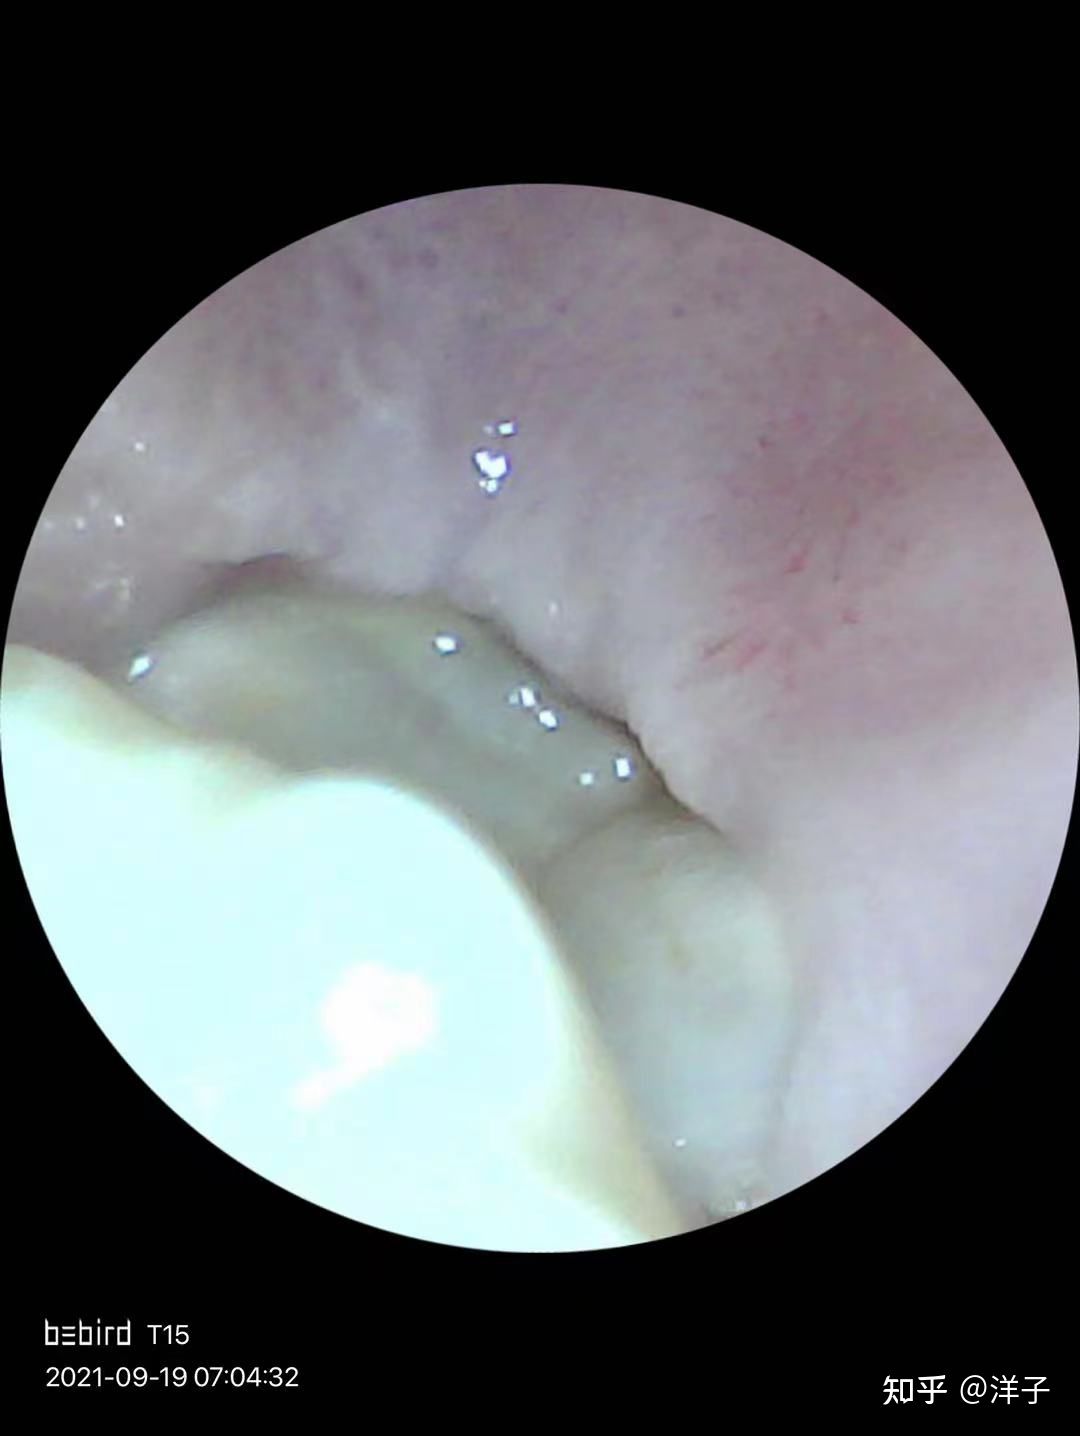

先上一个拔除前的图片。

强烈推荐拔牙前购买一个可以深入口腔看的采耳棒,普通最便宜的就可以。因为镜子实在不方便(我拔牙后开口受限,根本不能张嘴用镜子看)。

这里我是用之前买的一个可视化掏耳勺,用口腔模式拍摄的。平时用来掏耳朵,没想到拔牙也用上了。

拔牙后每天我都会用这个看一看牙齿情况拍个照,看伤口情况,看牙洞里是否掉落了食物。后面的因为太过于血腥就不放图片出来了。